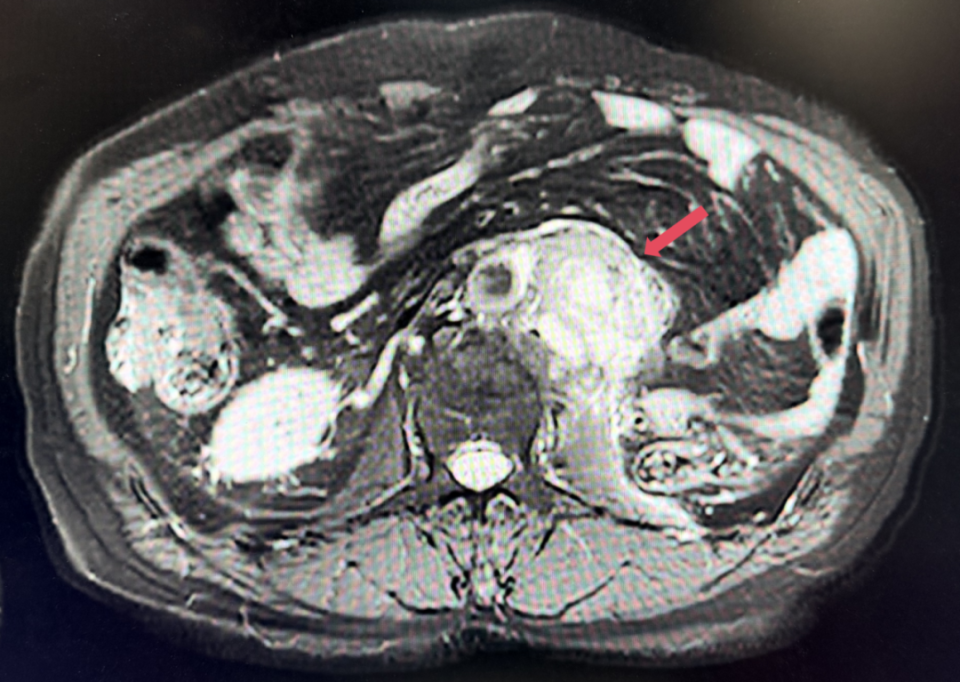

2023年11月,最深应答

2023年11月:治疗10个月(C15)评估,肿瘤负荷减少至41mm,维持PR。